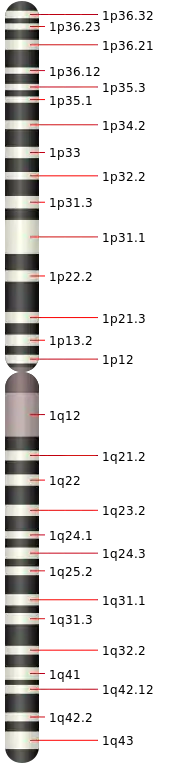

Because Urbach–Wiethe disease is an autosomal recessive condition individuals can be carriers of the disease but show no symptoms. The disease is caused by loss-of-function mutations to chromosome 1 at 1q21, the extracellular matrix protein 1 (ECM1) gene.[12] The dermatological symptoms are caused by a buildup of a hyaline material in the dermis and the thickening of the basement membranes in the skin.[9] Urbach–Wiethe disease is typically diagnosed by its clinical dermatological manifestations, particularly the beaded papules on the eyelids. The discovery of the mutations within the ECM1 gene has allowed the use of genetic testing to confirm an initial clinical diagnosis. Periodic acid-Schiff (PAS) and immunohistochemical staining may also be used for diagnosis.[6][13]

Researchers have mapped Urbach–Wiethe disease to chromosome 1 at 1q21 and specifically identified the extracellular matrix protein 1 (ECM1) gene as the gene containing mutations that can lead to the development of the condition.[12] At this point, 41 different mutations within ECM1 have been reported to lead to Urbach–Wiethe disease.[13] These were all homozygous loss-of-function mutations (i.e. nonsense, frameshift or internal deletions).[9] It is an autosomal recessive condition,[2][13] requiring two mutated copies of the ECM1 gene to cause the disease.[20]